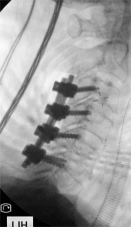

7. 复杂脊柱骨折内固定技术

随着区域内社会经济开发,复杂严重脊柱脊髓损伤病例增加,如何良好的手术治疗解除脊髓压迫、重建脊柱稳定性,使患者创伤最小、收益最大是促进患者康复至关重要的一环。皇冠娱乐城

已熟练开展各类脊柱损伤修复重建技术,每年完成复杂脊柱骨折手术处于区域领先水平。